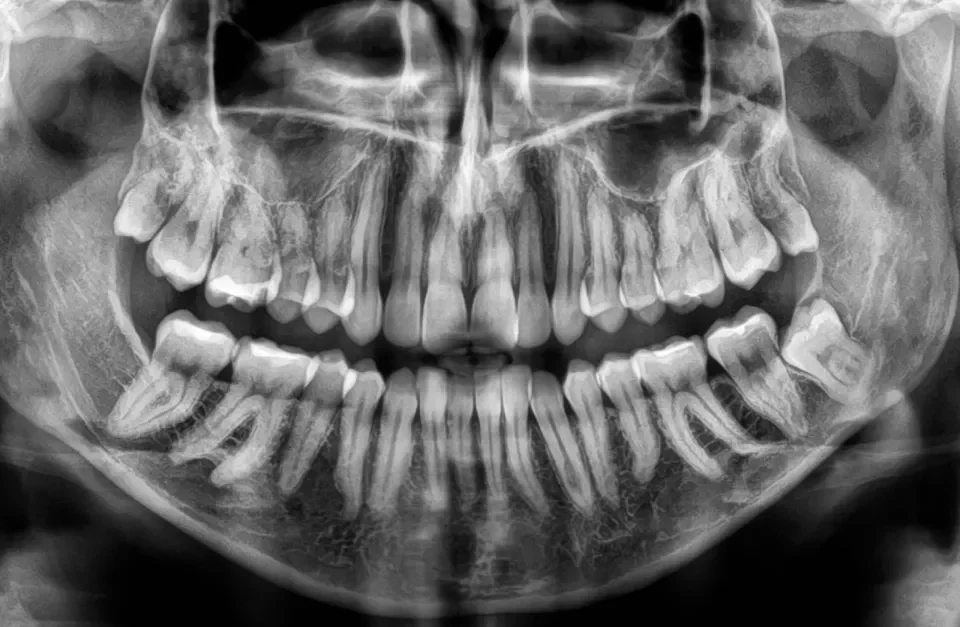

MOSTY ZĘBOWE Wiele osób w pewnym momencie życia staje przed koniecznością usunięcie zęba lub założenia korony ,gdyż własny ząb jest mocno zniszczony. W takim wypadku z pomocą przychodzi lekarz protetyk czyli specjalista w dziedzinie odbudowy zębów na wzór naszych naturalnych. RODZAJE […]